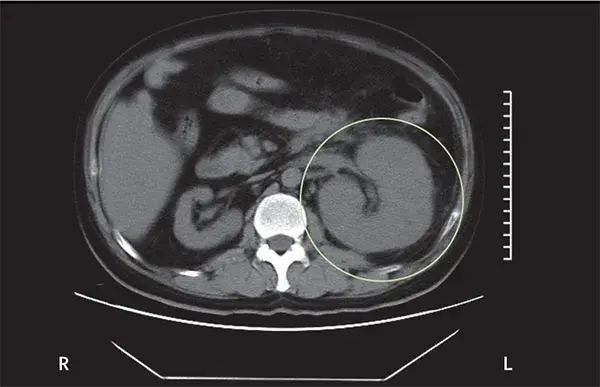

Mudança dinâmica do tamanho renal?

Mudança dinâmica do tamanho renal?Um homem de 39 anos foi internado no hospital com história dia com dor no flanco esquerdo e tontura há um dia. Paciente tinha antecedentes de diabetes mal controlado e nefrolitíase obstrutiva é esquerda. Após avaliação inicial a TC do abdome mostrou aumento do tamanho do rim esquerdo devido gás no parênquima renal, espaço perirrenal

Valkercyo Feitosa